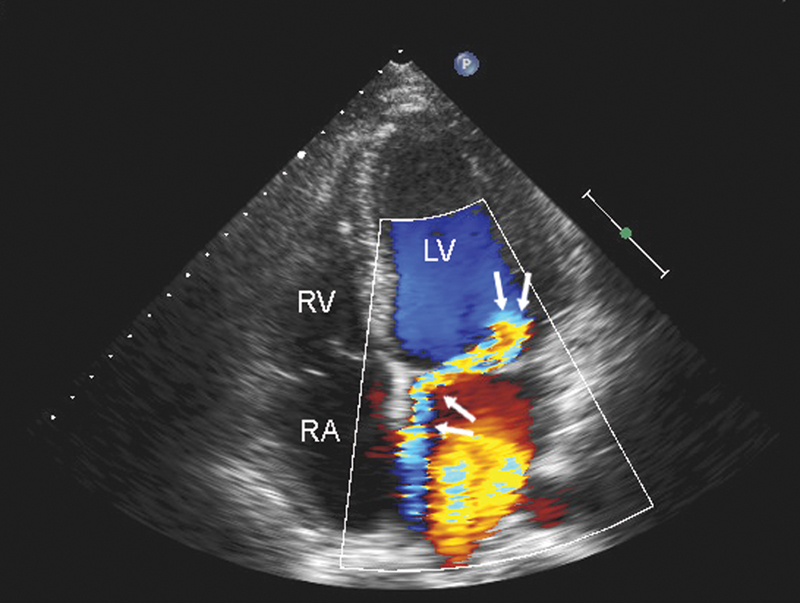

فحوصات تشخيصية لبعض امراض القلب والشرايين التاجية